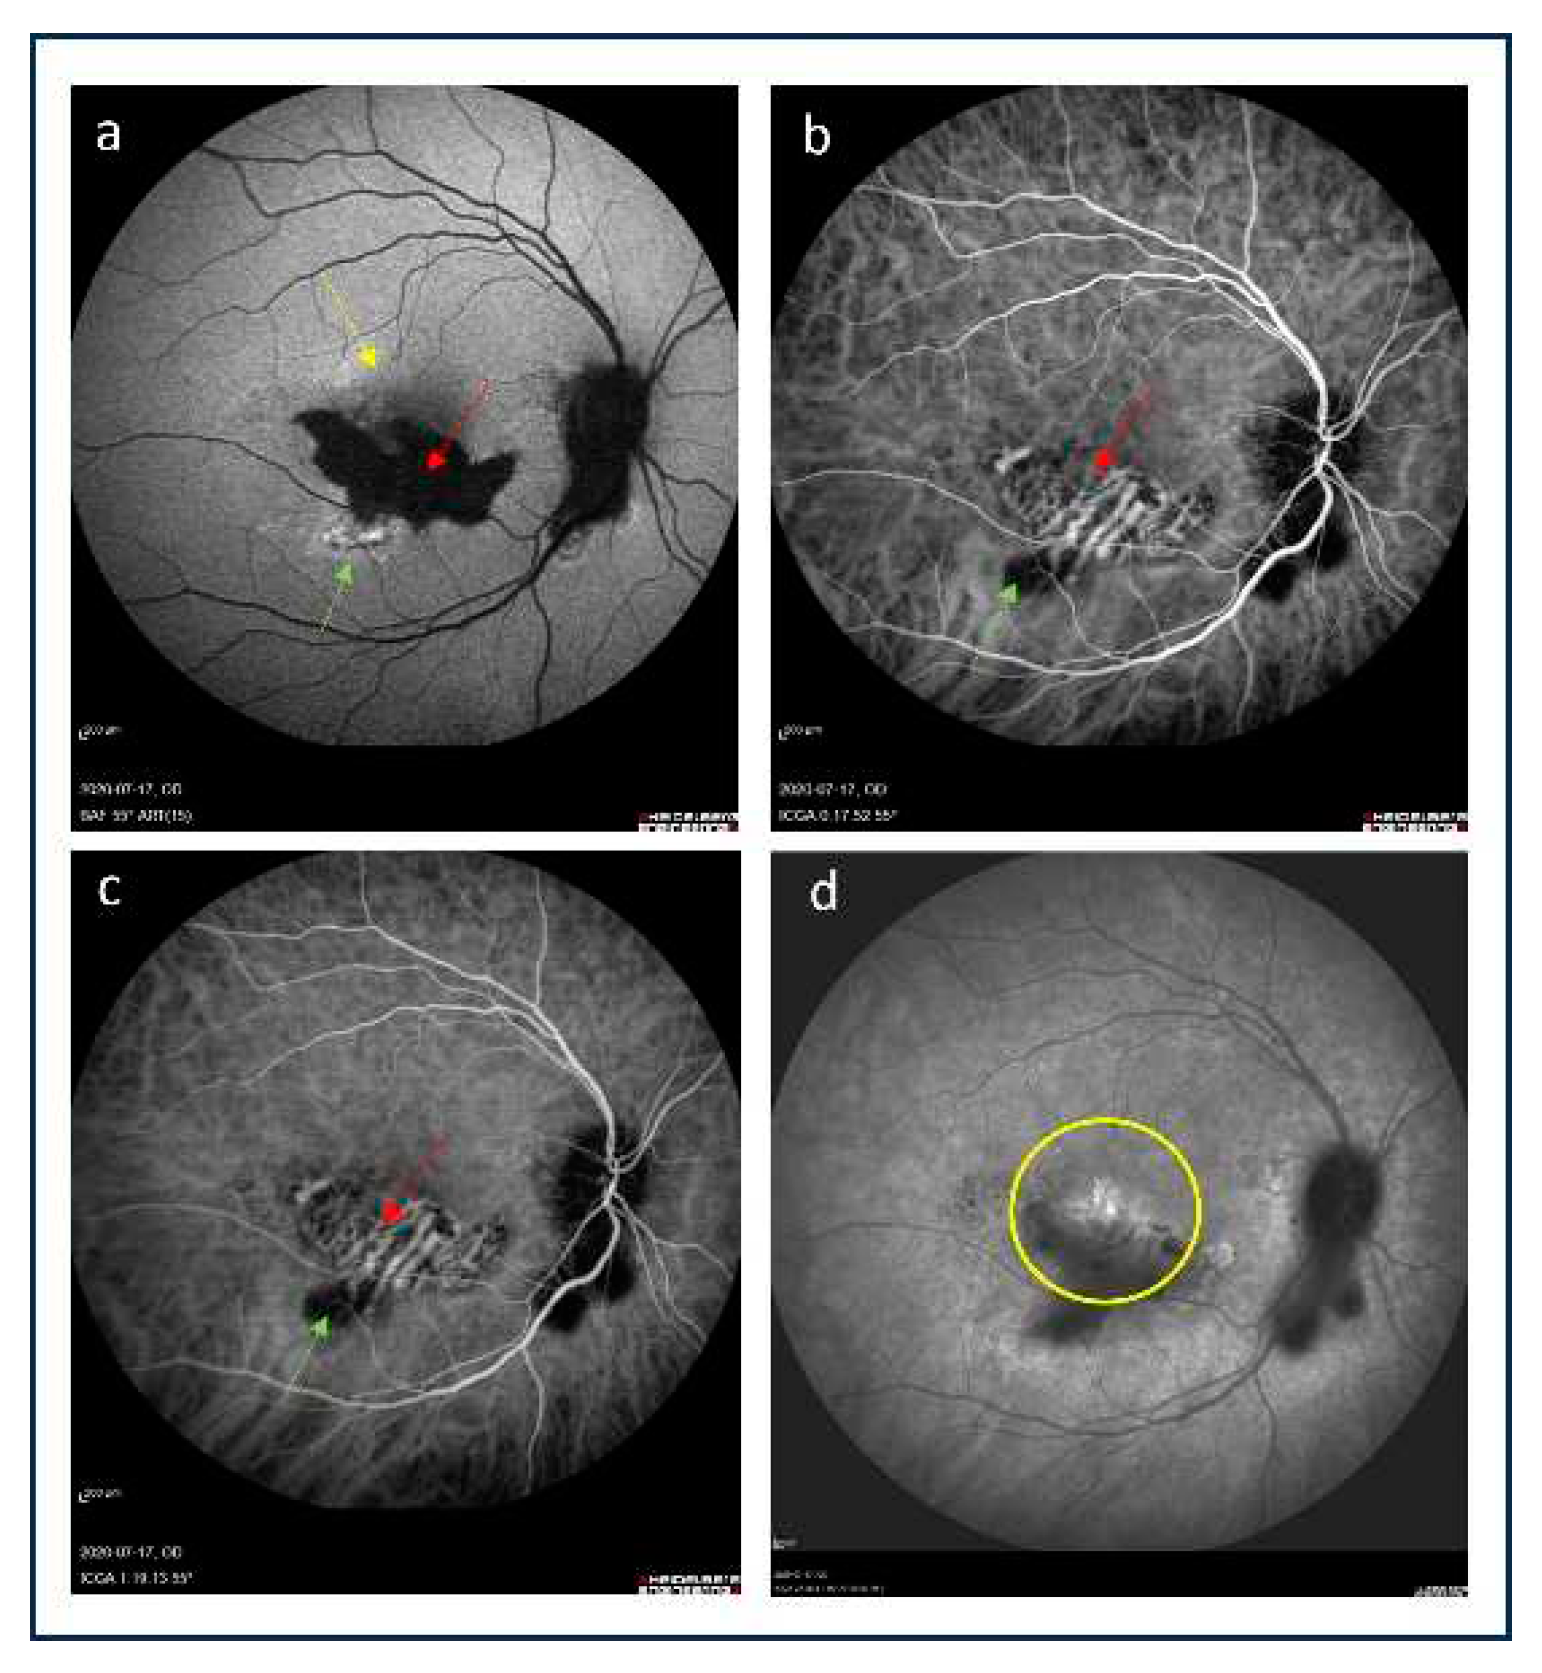

2.1. Fluorescein angiography

2.2. Indocyanine green angiography

2.5. Near-infrared autofluorescence imaging